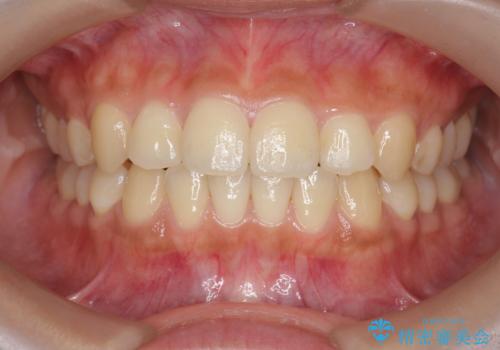

【モニター】八重歯と前歯のクロスバイト ワイヤーを併用しインビザラインで矯正治療